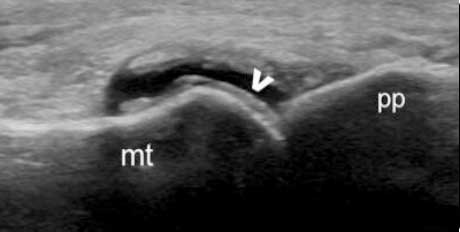

“双轨征”

跖趾关节软骨表面可见高回声不规则增强的软骨滑膜边缘线,呈“双轨征”。

高回声带

软骨表面回声增强,与深面的骨性关节面强回声线形成“双轨征”。

肌骨超声可通过高清影像图判定软骨表面有无出现一条与强回声骨皮质平行的线样强回声,即“双轨征”这一痛风性关节炎特征性表现,判定疾病所属。当尿酸盐粘附并沉积于漂浮的滑膜上时,超声检查可在关节腔内发现漂浮的高亮回声;而当尿酸盐长期沉积于韧带上时,在超声中即显示条带状的略高回声(韧带)中出现高回声点、高回声带或高回声团块(尿酸盐),从而判断痛风病情处于哪一时期。